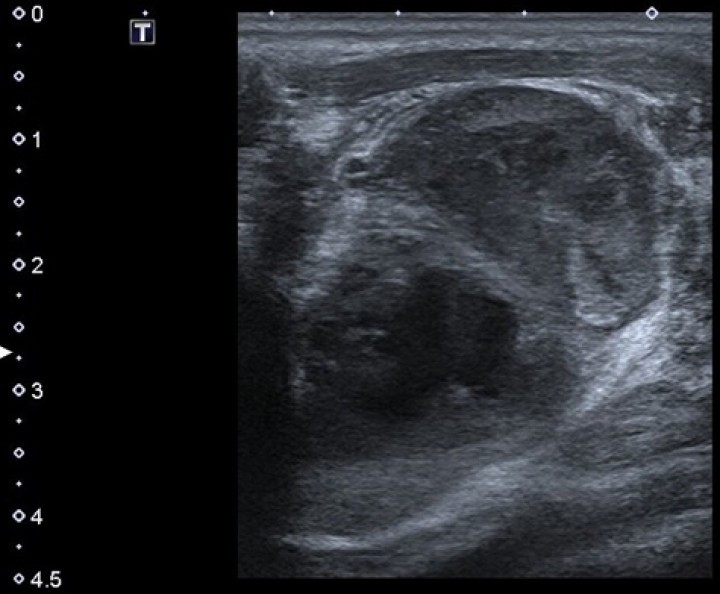

El LN y el tejido circundante se enviaron para estudio histopatológico, observándose un denso infiltrado inflamatorio mixto, con predominio de neutrófilos y macrófagos ocasionales. Además, se realizó una tinción PAS (ácido peryódico reactivo de Schiff) para evidenciar hongos, y tinción Giemsa para ayudar en la visualización de posibles microorganismos. No se observaron microorganismos con ninguna de las tinciones mencionadas. La interpretación fue severa celulitis supurativa y necrotizante activa con linfadenitis asociada (Fig. 6).

<p>(<strong>A</strong>) Microfotografía de sección tisular de la masa, mostrando estructura histológica de linfonodo. (<strong>B</strong>) Se observa imagen a mayores aumentos, consistente con linfadenitis neutrofílica. (Hematoxilina-Eosina; objetivos de 10x y 40x).</p>

Figura 6

(A) Microfotografía de sección tisular de la masa, mostrando estructura histológica de linfonodo. (B) Se observa imagen a mayores aumentos, consistente con linfadenitis neutrofílica. (Hematoxilina-Eosina; objetivos de 10x y 40x).